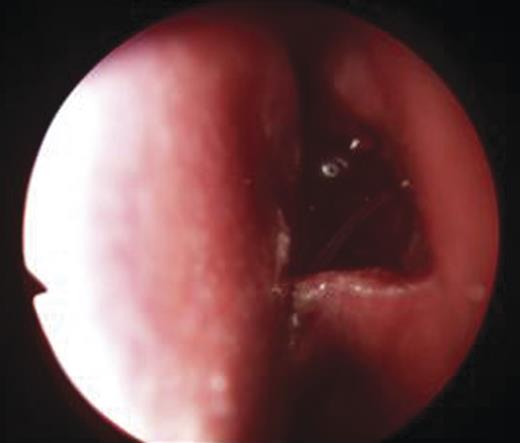

- An endoscopic left anterior ethmoidectomy was performed (Fig. 9) with marsupialisation of the mucocele (Fig. 9) and trimming of the DCR stent (Fig. 10)

Figure 10:Post-operative view with trimmed DCR stent in situ in the left nasal cavity.

Post-operatively, she was discharged the next day and advised to administer chloramphenicol eyedrops as well as betnesol nasal drops for a week. The DCR stent remained in situ for 3 months and was removed in the clinic. There was clinical resolution of the medial canthal swelling and epiphora.